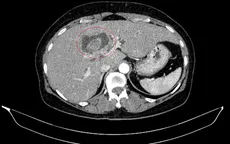

Hiếm gặp: Bệnh nhân mắc đồng thời hai ung thư nguyên phát VTV.vn - Các bác sĩ Bệnh viện Bạch Mai vừa phát hiện một bệnh nhân nữ mắc đồng thời ung thư đại tràng phải và ung thư đường mật trong gan.

Cẩn trọng: Vàng da có thể là một dấu hiệu của ung thư đường mật VTV.vn - Ung thư đường mật có dự hậu rất xấu, đặc biệt là ung thư vùng rốn gan. Nếu không điều trị, bệnh nhân tử vong do suy gan và di căn trong vòng 3 - 6 tháng.